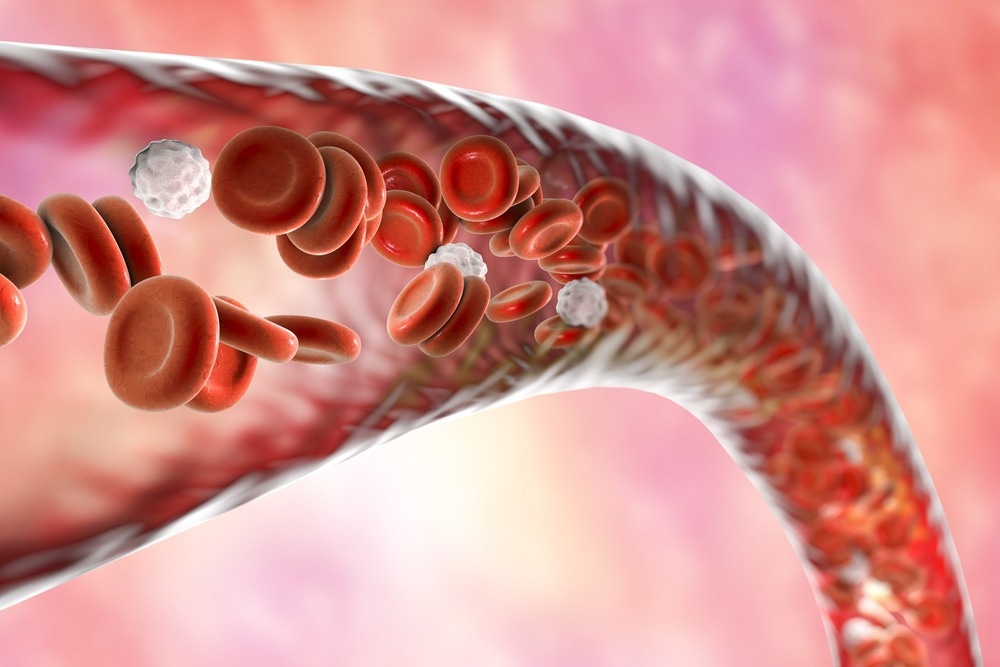

מומים עורקים ורידים, סימן היכר של טלנגיאקטזיה דימומית תורשתית, עשויים להיות מונעים על ידי האצת מחזור תאי האנדותל באמצעות CDK6,

מומים עורקים ורידים, סימן היכר של טלנגיאקטזיה דימומית תורשתית, עשויים להיות מונעים על ידי האצת מחזור תאי האנדותל באמצעות CDK6,